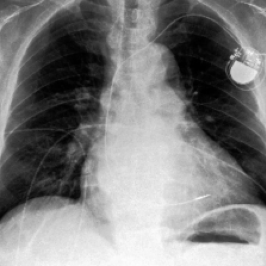

Waterbirds (Sagawa et al., 2020) is an image classification dataset where bird types are associated with a spurious background attribute (water or land). CelebA (Liu et al., 2015) is an image classification dataset, where hair color is an imbalanced attribute with respect to gender. MultiNLI (Williams et al., 2018) is a text benchmark of categorizing two sentences as entailing each other, contradicting each other, or neutral. The spurious correlation is between negation words like “never” and the “contradiction” label. CivilComments (Borkan et al., 2019) is a toxicity text classification dataset containing underrepresented demographic groups. CheXpert (Irvin et al., 2019) is a large-scale medical dataset of chest radiographs with rare pathologies, especially amongst certain minority groups.